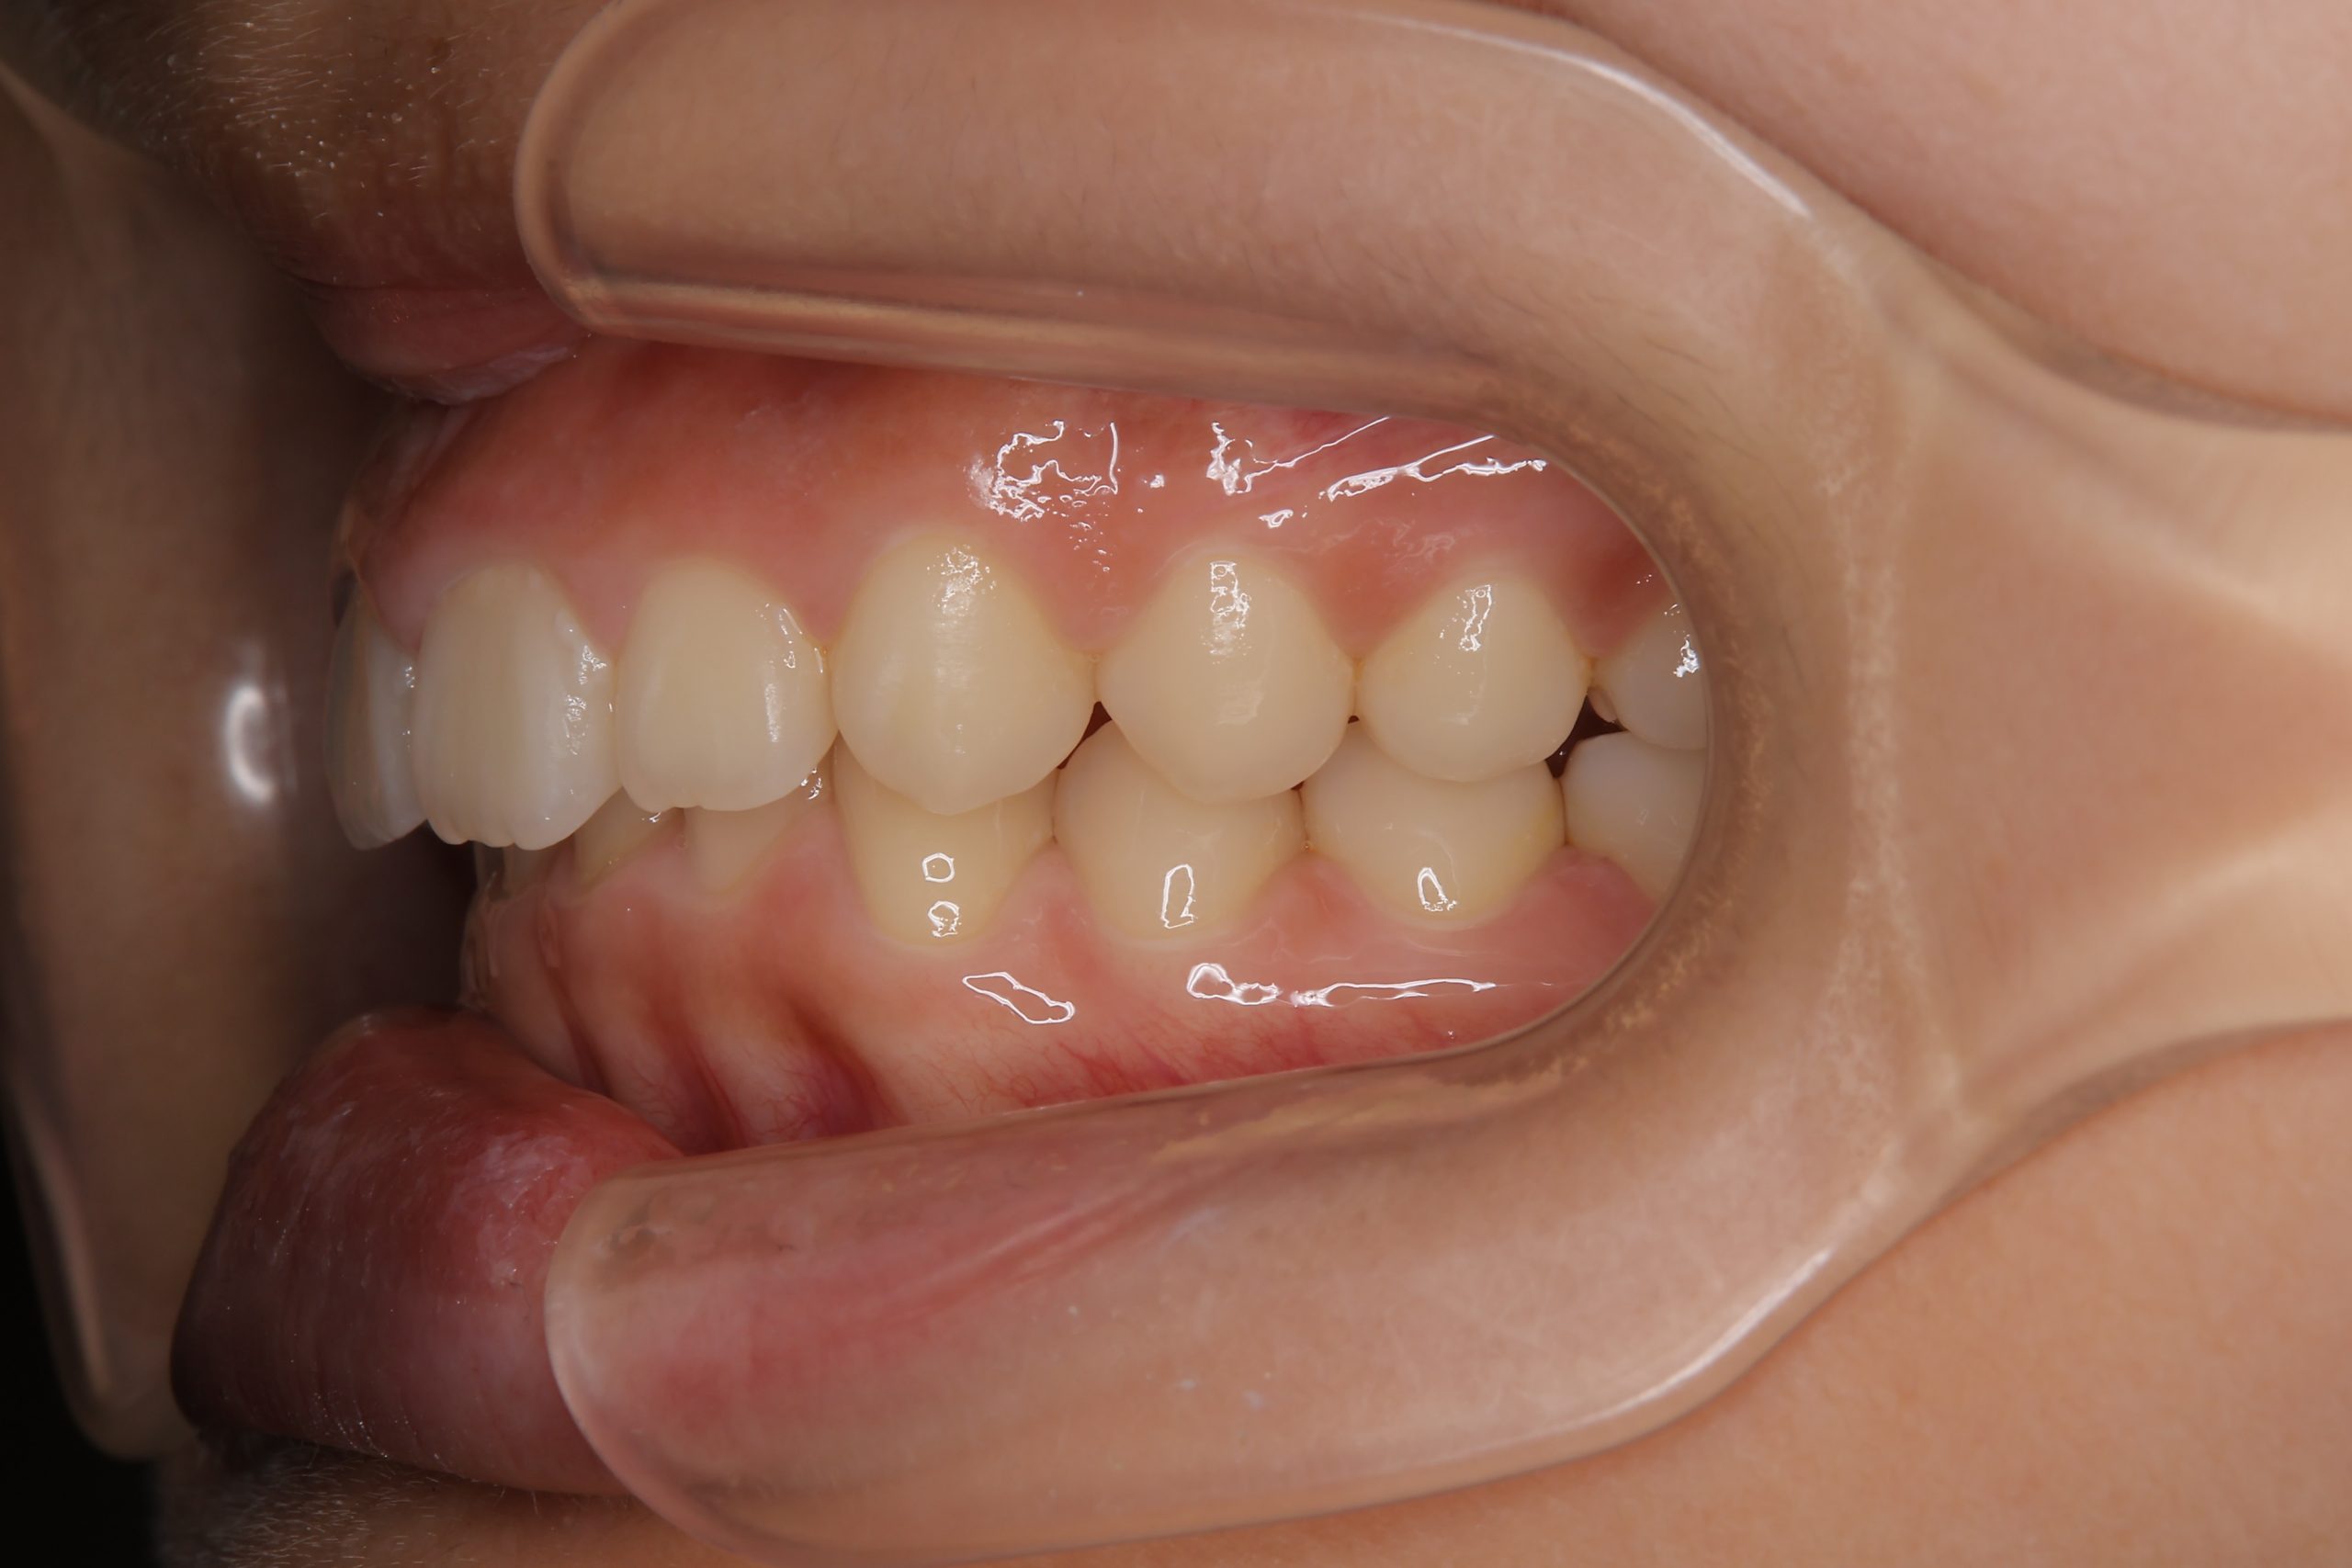

子どもの矯正治療|症例_547 Case

ビフォー

主訴 上下の歯が接触しない

施術内容 上顎急速拡大装置と下顎リンガルアーチを用いて上下顎骨を拡大した。

その後マウスピース型矯正装置で歯牙を配列し良好な咬合を獲得した。

治癒期間 2年10か月